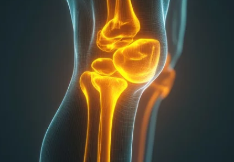

1. 오금 통증의 주요 원인

✔ 근육 & 인대 손상 – 과도한 운동, 부상으로 인해 발생 가능

✔ 연골 손상 – 반월상연골판(무릎 연골) 손상으로 인해 무릎 뒤쪽 압박감 유발

✔ 베이커 낭종 – 무릎 뒤쪽에 물이 차서 생기는 혹(부종 유발)

✔ 좌골신경통 – 허리 디스크 등으로 인해 무릎 뒤쪽까지 저림 & 통증 발생

✔ 혈관 문제 – 혈전(혈액 응고)으로 인해 오금 부위에 통증 및 부종 발생 가능

📌 즉, 오금 통증의 원인은 근육 손상, 연골 문제, 신경 이상, 혈관 문제 등 다양할 수 있다.